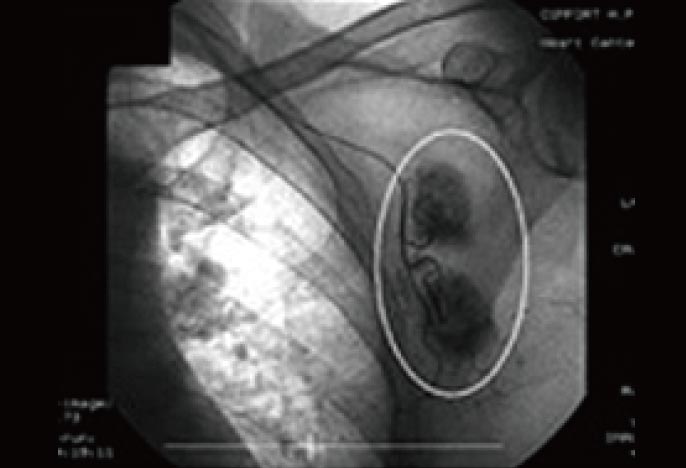

治療前に、血管カテーテルから造影剤を入れて、転移したがんそのものを調査した時の両像です。

わきの下の太い血管周囲に、もやもやとしたがんの新生血管が密に認められます(円の中の黒々とした部分)。当然ここまで進んでしまうと抗がん剤や放射線治療など、いわゆる保険治療で実施される標準治療自体、根治の見込みはありません。まさに“治療の手立てなし”という状況です。推定された予後寿命は、およそ3ヶ月から1年程度。保険治療、あるいは細かい調整の一切不可能な民間療法だけに頼っていたのでは、まもなくホスピス・緩和ケア病棟への入院も予想されました。